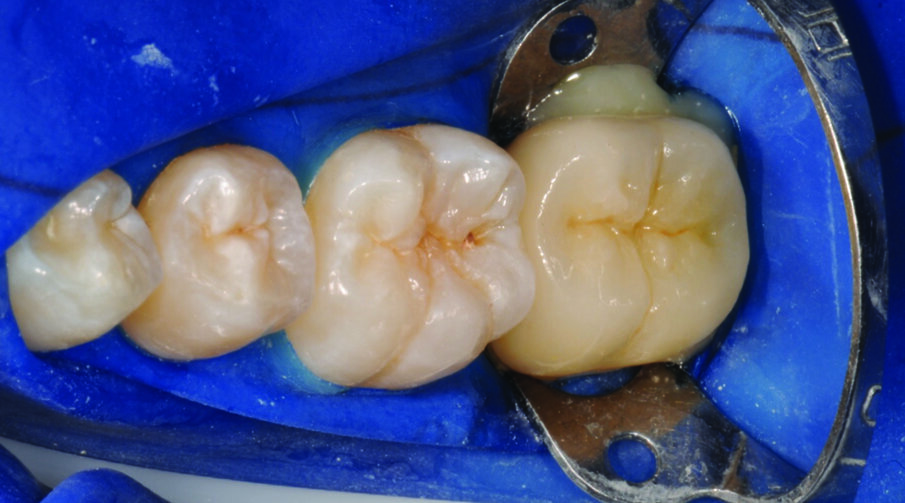

Fig. 6: Tooth preparation after rubber dam placement for isolation.